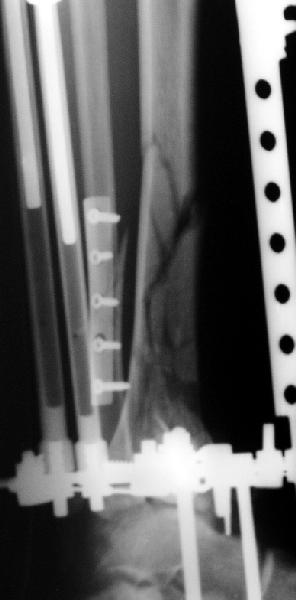

Пластинка красивая. Чуть только спереди назад идет, не сосем по оси большеберцовой кости. А там не маловато фиксаторов собственно в дистальном суставном конце кости? А вправляли его как? Как будто или осталось запрокидывание кзади или недонизведен передний край. Но с учетом исходного тяжелейшего повреждения - все равно здорово.

Мне кажется, что все дискутирующие согласным с одним - надо воостанавливать в данной ситуации суставную поверхность. Сделать это закрыто (когда суставная поверхность состит из 3-фрагментов)лично для меня не реально. Конечно можно открыто отрепонировать, зафиксировать спицами и оставить в аппарате, но роль аппарата и выполняет LSP. Разрез в области внутренней поверхность голеностопного сустава и небольшой разрез в ср/3 голени для проксимальных винтов, надкостница не обдирается, пластина вводится подкожно.

Вид конечности на следующий день после операции.